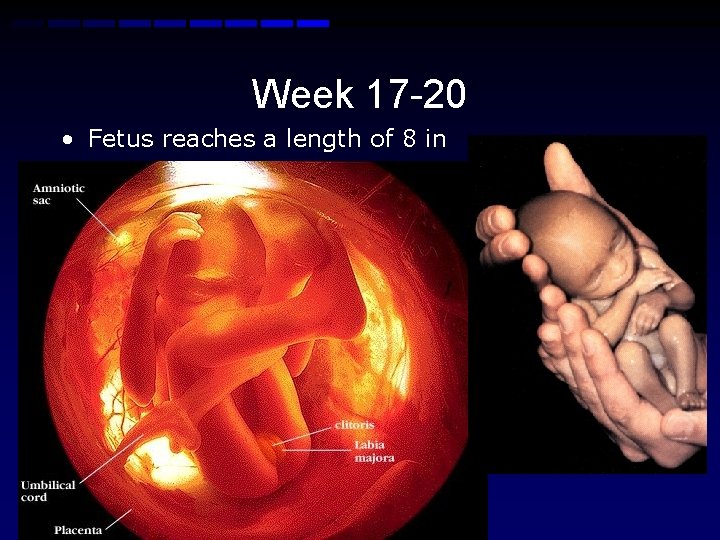

Week 17 -20 • Fetus reaches a length of 8 in • Lanugo hair covers entire body • Eyebrows and lashes appear • Nails appear on fingers and toes • Fingerprints formed • More active with increased muscle development-mom can feel the fetus moving • Taste buds formed